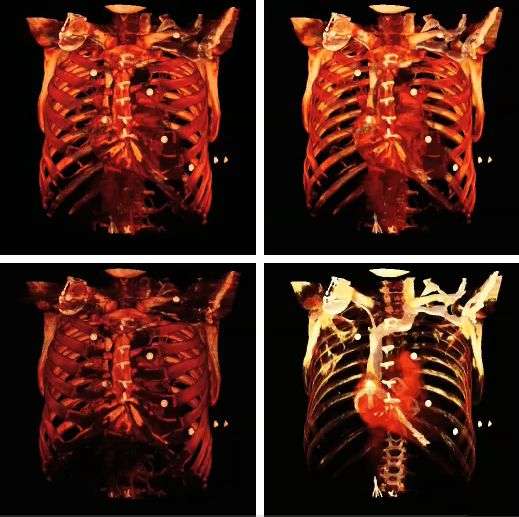

The influence of the opacity table is illustrated in the following example images: